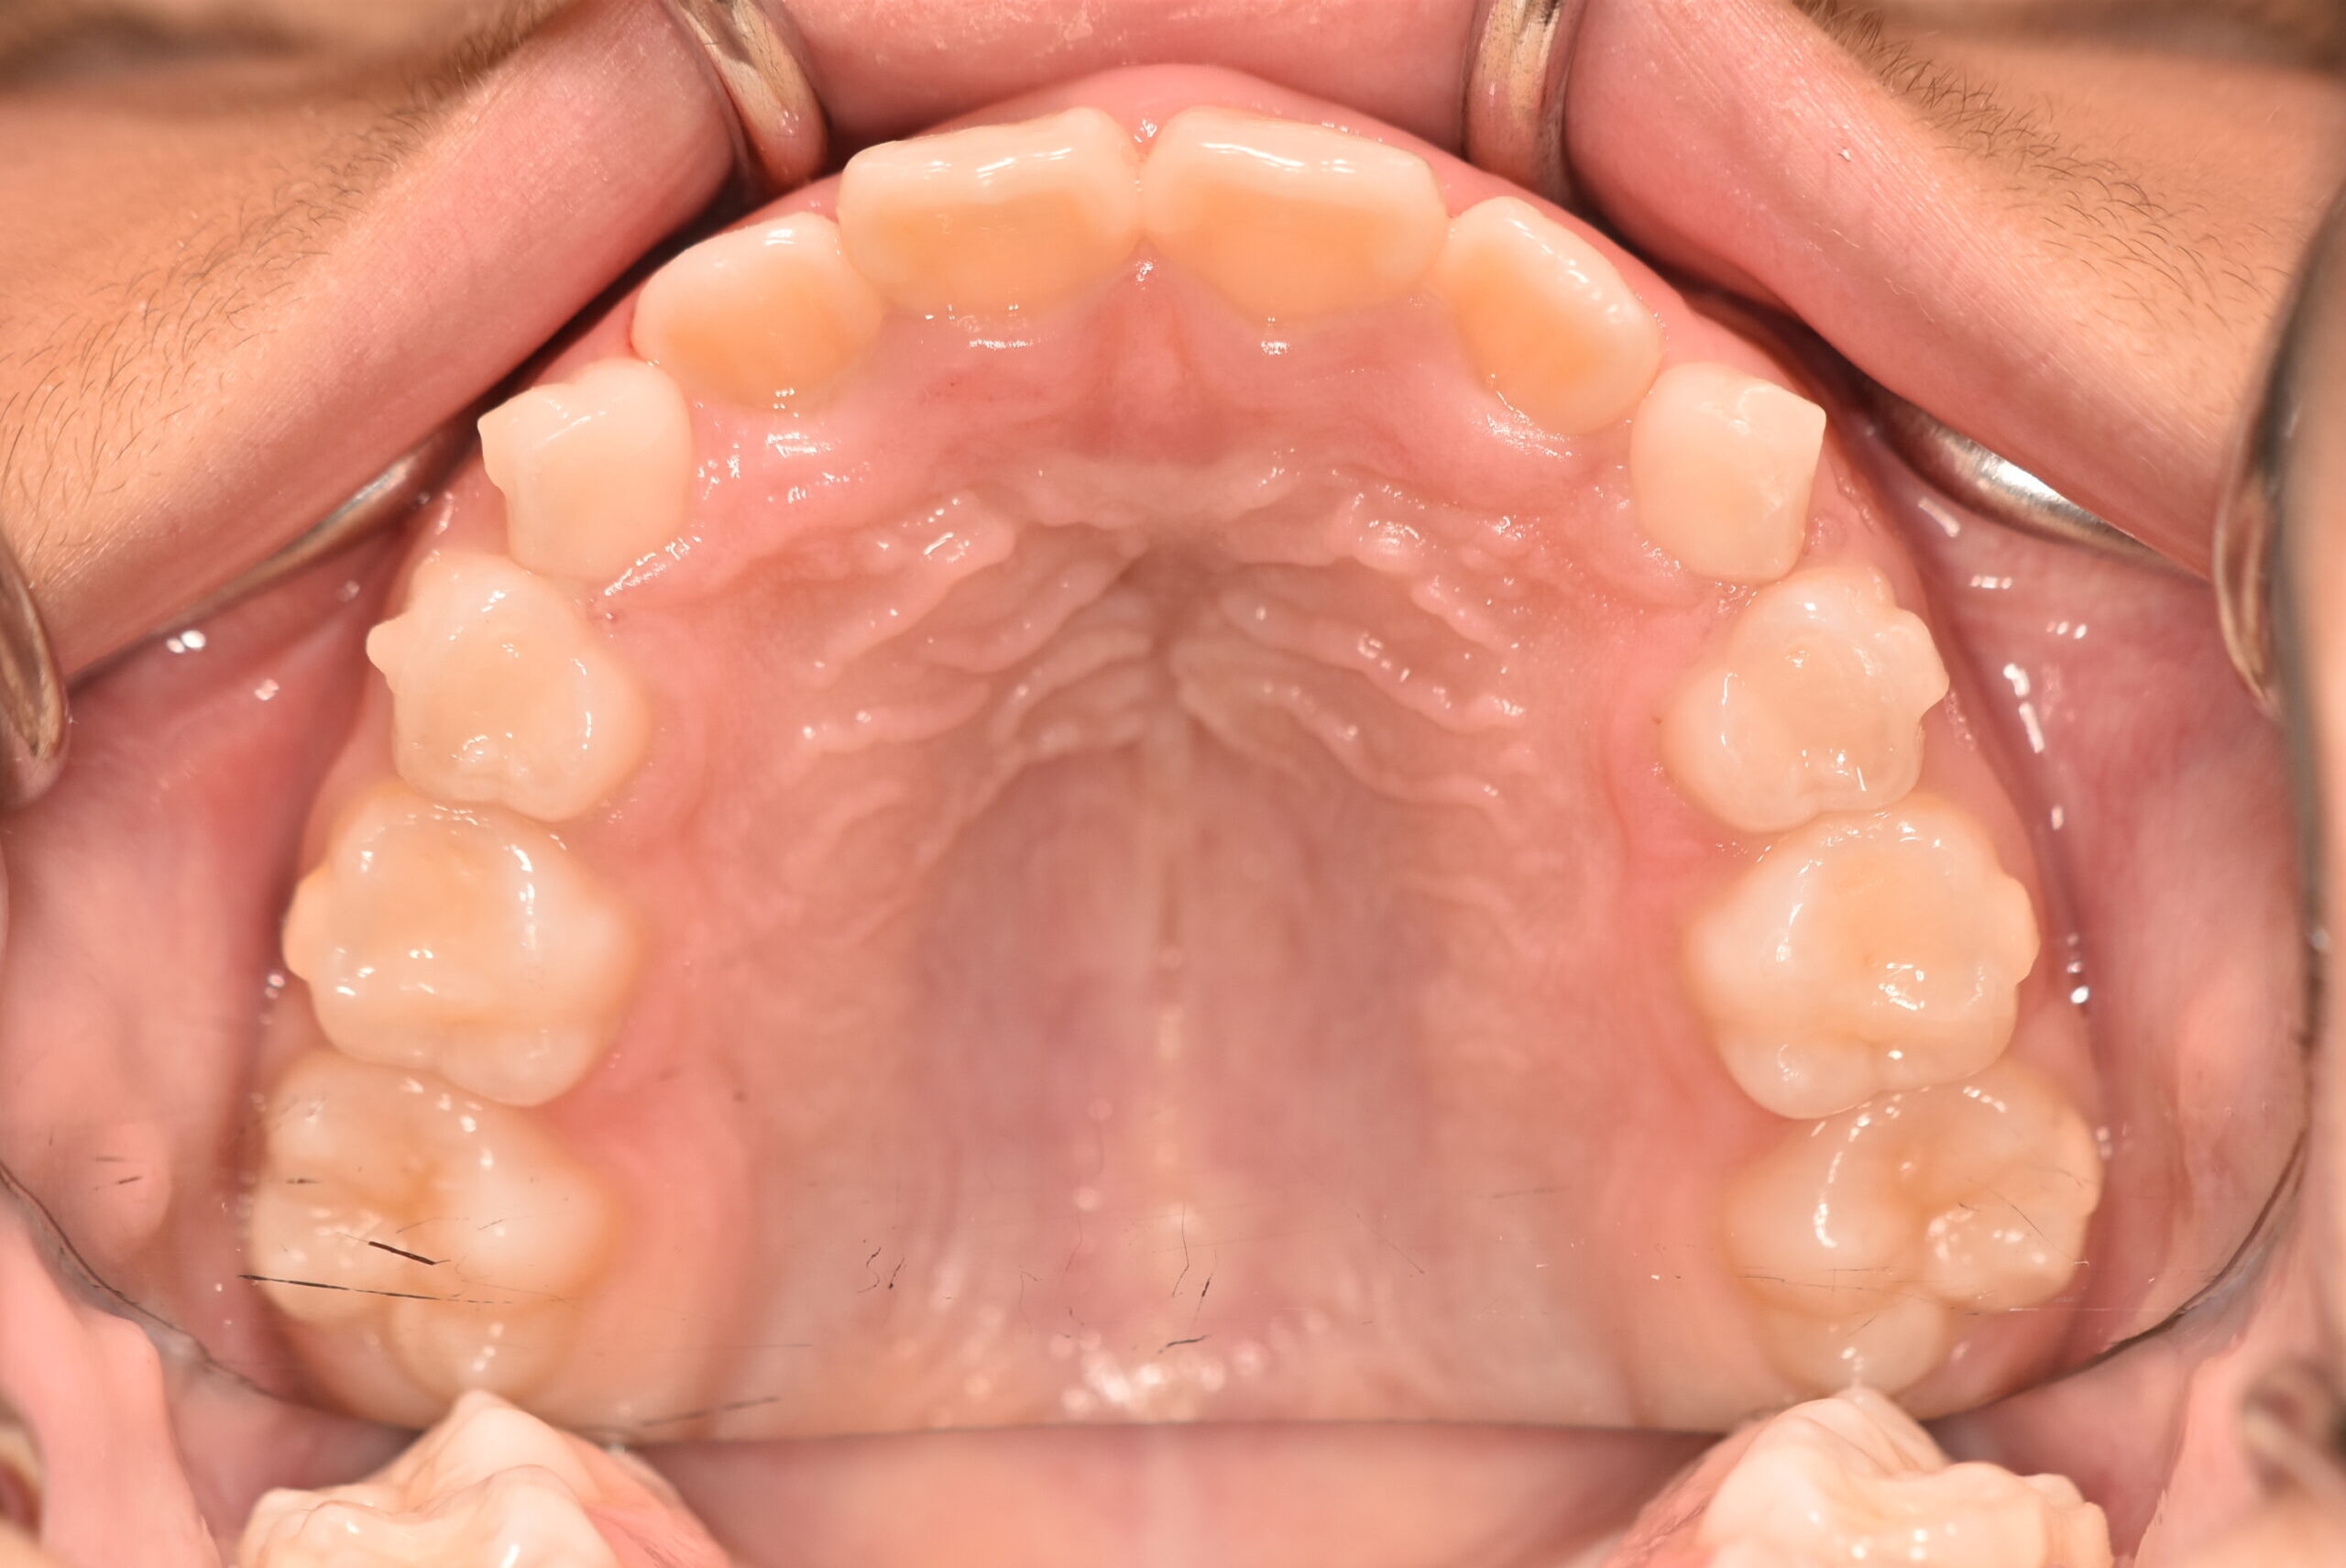

初診時

症例 症例 症例 症例

年齢

9歳 性 別 女性

治療内容の詳細 初診時9歳の女児で、歯のがたつきを気にされ来院されました。

検査の結果、前歯部叢生を伴うアングルⅠ級不正咬合と診断しました。

治療としてはマウスピース矯正(インビザラインファースト)で配列を行い、上下顎の側方拡大と萌出スペースを確保しました。